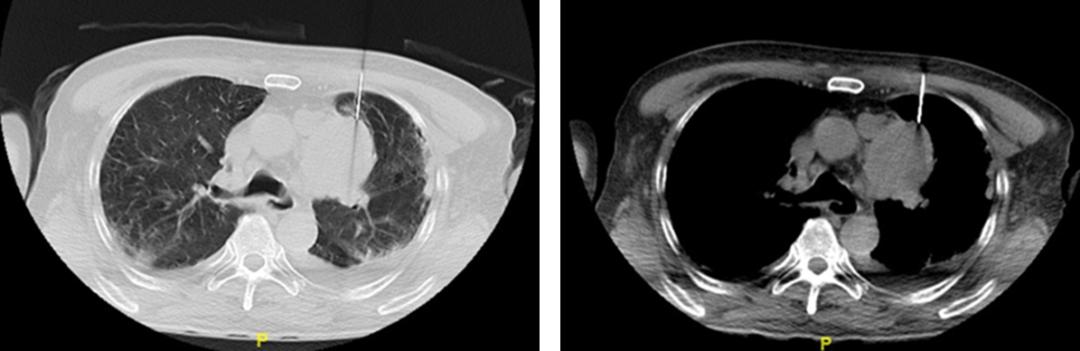

患者于2022年11月7日行CT引导下经皮穿刺肺活检(图3),后病理结果显示送检组织镜下为少许血凝块及肺泡组织,其间可见少量游离异型深染小圆细胞,参考免疫组化结果及患者影像学, 为小细胞恶性肿瘤,考虑小细胞神经内分泌癌 (图4、5)。 因患者自身抗体提示,抗TIF1γ抗体lgG+++、抗RO-52抗体lgG+++、抗核抗体ANA+1:320(核颗粒型),故诊断为特发性炎性肌病——肿瘤相关性肌炎。

图3

针对炎性肌病,在临床上全面评估患者情况后遵循个体化原则,首选糖皮质激素,泼尼松1mg/(kg.d)。患者2022年11月11日出现腹痛,CT提示小肠不全梗阻,附见肺气肿伴肺大泡形成,两侧存在胸腔积液并以左侧为著;肝及右肾囊性灶;左肾小结石;躯干皮下复发软组织水肿(图6)。因患者小细胞肺癌广泛期,合并小肠梗阻,一般情况差,无法耐受化疗及肿瘤的相关治疗,与患者家属沟通病情后,暂未行肿瘤的病因治疗。